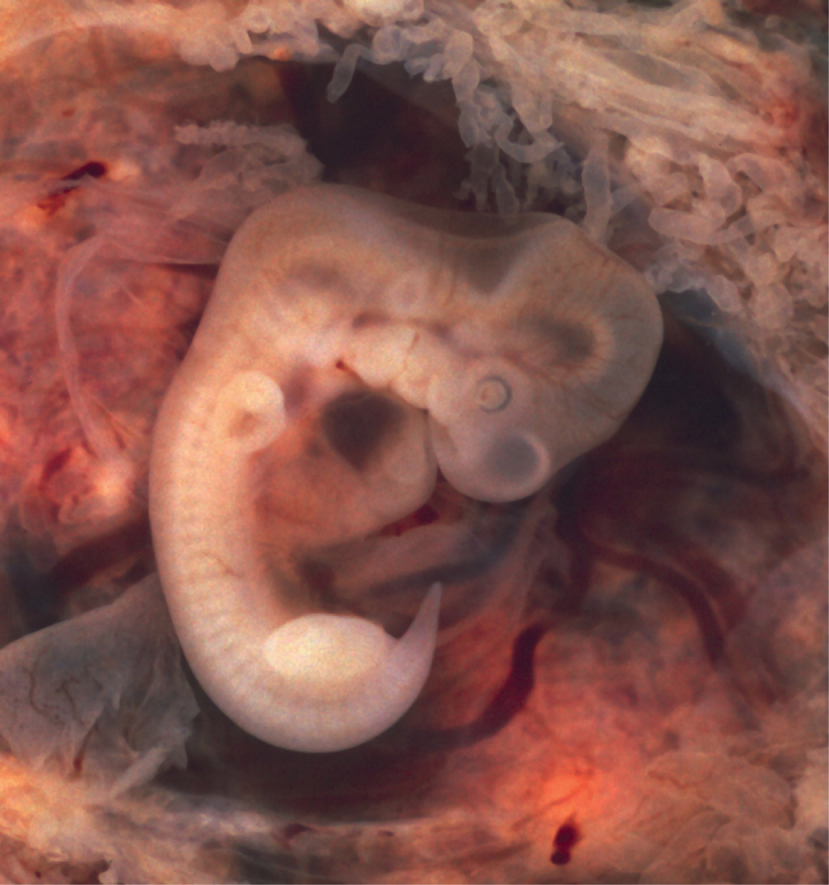

Within the first 8 weeks of gestation, a developing embryo establishes the rudimentary structures of all of its organs and tissues from the ectoderm, mesoderm, and endoderm. This process is called organogenesis. The nervous system and heart are being formed. The heart begins beating in the beginning of the fourth week. During weeks 4–5, the eye pits form, limb buds become apparent, and the rudiments of the pulmonary system are formed. During the sixth week, uncontrolled fetal limb movements begin to occur. Paddle-shaped hands and feet develop fingers and toes by the process of apoptosis (programmed cell death), which causes the tissues between the fingers to disintegrate. A tail also appears, reflecting our shared ancestry with other vertebrates, but later also disintegrates. By week 7, the facial structure is more complex and includes nostrils, outer ears, and lenses (Figure 20). By the eighth week, the head is nearly as large as the rest of the embryo’s body, and all major brain structures are in place. The external genitalia are apparent, but at this point, male and female embryos are indistinguishable. Bone begins to replace cartilage in the embryonic skeleton through the process of ossification. By the end of the embryonic period, the embryo is approximately 3 cm (1.2 in) from crown to rump and weighs approximately 8 g (0.25 oz).

Figure 20. Embryo at 7 Weeks. An embryo at the end of 7 weeks of development is only 10 mm in length, but its developing eyes, limb buds, and tail are already visible. (This embryo was derived from an ectopic pregnancy.) (credit: Ed Uthman)